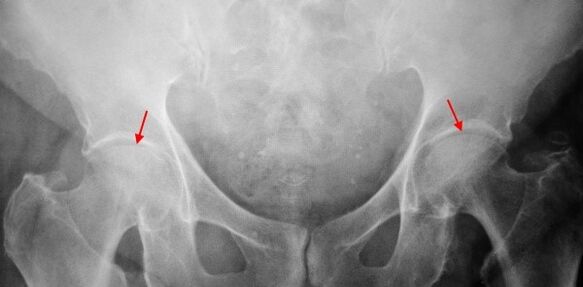

X. mailako koxartrosia duen pazientearen gainean, aldaketa epelak dira, aldaketa arinak: aldakorreko aldea estutzen da, baita azetabuloaren kanpoko edo barneko ertzaren inguruan hezur hazkuntzak, femurraren burutik eta lepotik aldaketarik ezean.

X -2 mailan irudiak 2. graduko koxartrosia da, bateriaren hutsunea murriztea (altuera normaletik erdia baino gehiago) zehazten da. Buru femorala gorantz desplazatu da, deformatua eta tamaina handitzen da, eta bere sestrak irregularrak dira. Coxartrosia maila honekin hezur-hazkuntzak barnealdean ez ezik, azetabuloaren kanpoko ertzean ere agertzen dira eta kartilagotik kanpora joaten dira.

3. graduko koxartrosiaren erradiografietan, biztanleen arteko lotura zorrotza, izterreko burua eta hezur hazkunde anitz hautematen dira.

Koxartrosiaren diagnostikoa ikasketa osagarrien seinale eta datu klinikoetan oinarritzen da, hau da, erradiografia da. Kasu askotan, X -Rays-ek koxartrosiaren maila ez ezartzea ahalbidetzen du, baita gertakarien kausa ere. Beraz, adibidez, lepoko angeluaren angelu-dihipsealaren gehikuntzak, azetabuloaren eszenak eta berdinketa displasia adierazten dute eta femurraren zati hurbilaren formaren aldaketak adierazi dira COKSartrosia Pertseko gaixotasunaren edo gazteen epifisiosiolisiaren ondorioa dela. Koxartrosia duten gaixoen erradiografietan, aldaketak ere detektatu daitezke lesioak adieraziz.